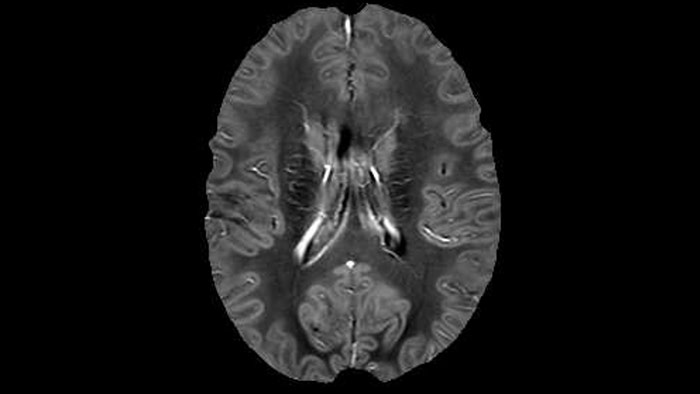

Dr. Rauscher says, “With better gradients we can use a shorter echo spacing on the spin echo, so we get better sampling of the rapidly decaying myelin signal, which typically has T2 of around 10-20 milliseconds at 3 Tesla. If we can reduce echo spacing from about 8 to 5-6 milliseconds, we get a much better sampling of the short decay component and increase our SNR, which is a big advantage. The same is true for multi-echo gradient echo which we use for susceptibility mapping and for mapping venous vessels in MS.”

He says the accelerated scanning is achieved via the use of Compressed SENSE and MultiBand SENSE. “We can use Compressed SENSE acceleration factors of about 10 on a 3D FLAIR for instance, which is quite remarkable compared with what we saw with the Achieva. With 3D FLAIR, we can push the spatial resolution to 0.3 cubic mm and it works. Previously, our 3D FLAIR scans lasted about 8 minutes, but now with Elition they are five minutes. The SNR is also visibly better. Our SWI and QSM scans look fantastic. Also, since a lot of neuroimaging is EPI based, using the MultiBand SENSE technique can increase temporal resolution and make it possible to run complicated DTI scans relatively quickly.”

QSM based on a Compressed SENSE multi-echo SWI.